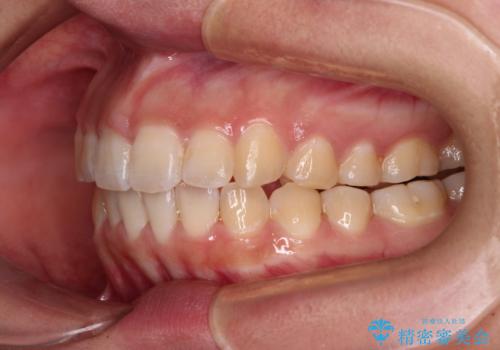

カリエールディスタライザーを併用したことで、確実かつ短期間で治療を終えることができました。